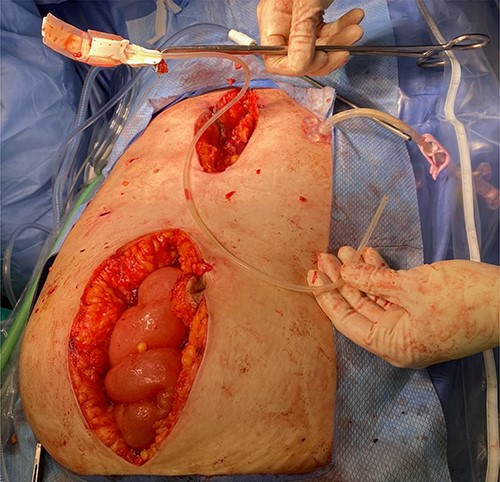

Diagnostic laparoscopy was initially carried out in hopes of identifying and removing the gastric band. However, adequate pneumoperitoneum was difficult to achieve due to minimal response to paralytic agents with increasing dosages presumably secondary to the patient’s underlying disease. As such, the decision was made to convert to laparotomy. A lower midline incision was made. The gastric band tubing was noted coursing over the ascending colon. This was traced down into the pelvis and an abscess cavity containing a large amount of purulent fluid was encountered. A swab of the fluid was sent for culture and sensitivity and the fluid, and it was then carefully suctioned and irrigated. In order to remove the gastric band, a separate upper midline laparotomy incision was made. Careful dissection was carried out until we were around the gastric band; its anchoring sutures were cut, and the band was freed from around the stomach. Interestingly, the band itself appeared to be infected and had a foul odor. The band along with the tubing was removed from the surgical field (Fig. 2). A Jackson–Pratt drain was placed in the pelvis to facilitate further drainage post-operatively. The patient tolerated the procedure well, her gastrostomy tube feeds were restarted on POD 1 and she had an uneventful recovery.